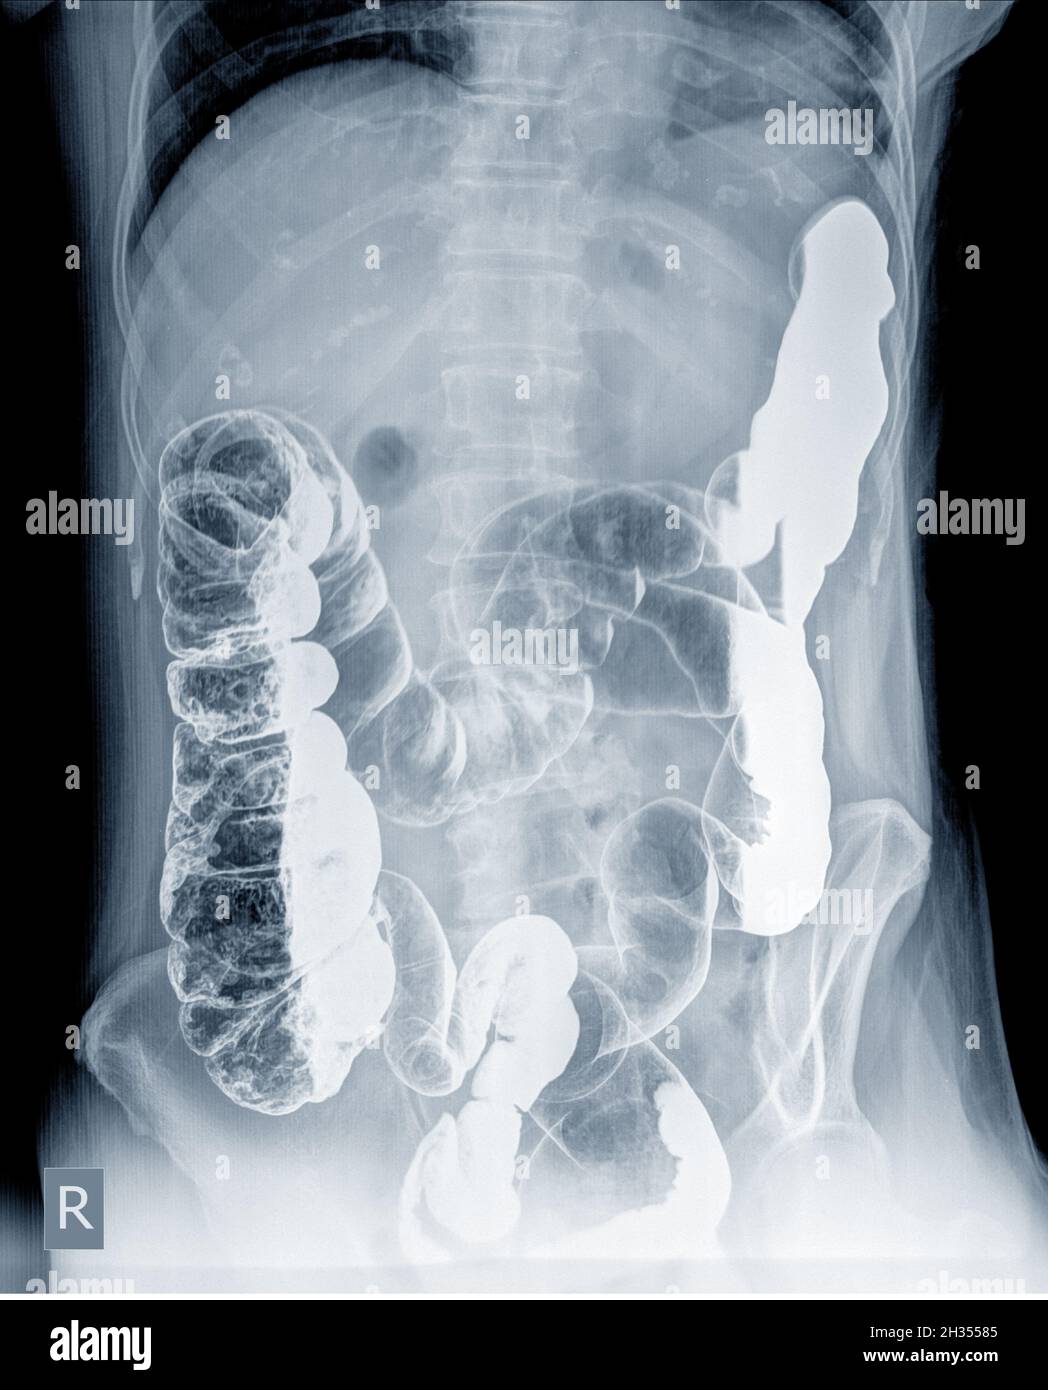

From www.sciencephoto.com

Barium Xray showing colonic diverticula Stock Image M140/0083 Is Barium X Ray Dangerous The risks of complications related to radiation exposure accumulate over. You may want to ask your healthcare provider about the amount of radiation used during the swallowing test. In each of the following tests,. You should ask your healthcare provider about the risks as they apply to you. The risks of a barium swallow test may include problems from radiation. Is Barium X Ray Dangerous.